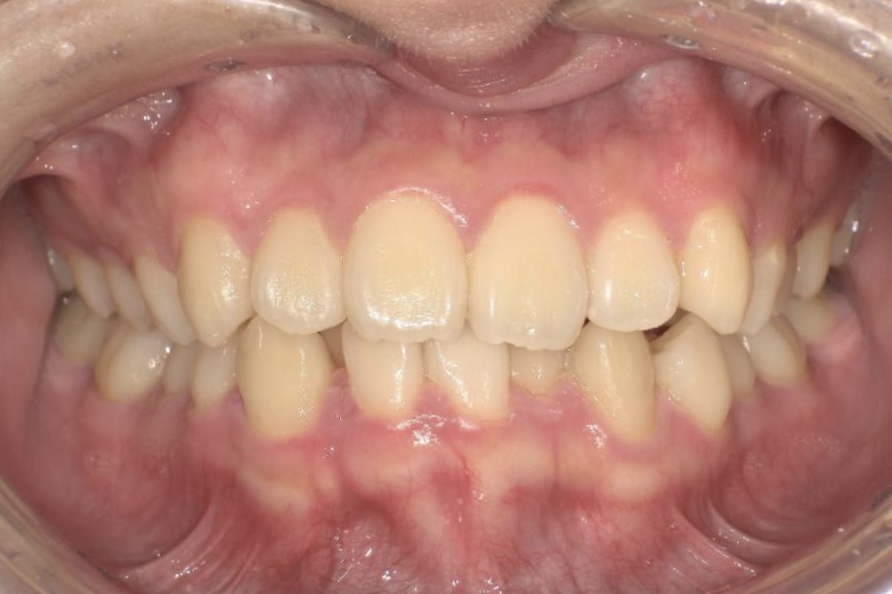

AFTER

治療は、マウスピース矯正インビザラインにて矯正治療を行い、歯列全体のバランスを考慮しながら計画を立てました。治療期間は1年4ヶ月で、歯並びがきれいに整っています。

見た目の自然さと治療中の快適さの両立を重視しながら、無理なく治療を進めることができた症例です。

| 年齢・性別 | 大学生女性 |

|---|---|

| 主訴 | ガタガタの歯並びが気になる |

| 施術内容 | 歯全体のマウスピース矯正システム「インビザラインアドバンス」を用いた治療 |

| 治療期間 | 1年4ヶ月 |

| 費用 | 1,034,000円(税込) |

| リスク/副作用 | 全ての方で、疼痛、咬合痛、歯根吸収、歯肉退縮、歯髄壊死が生じる可能性があります。 |

| その他注意点 | 指定した時間、マウスピースをつけていただけない場合は治療期間が長くなる場合があります。 |